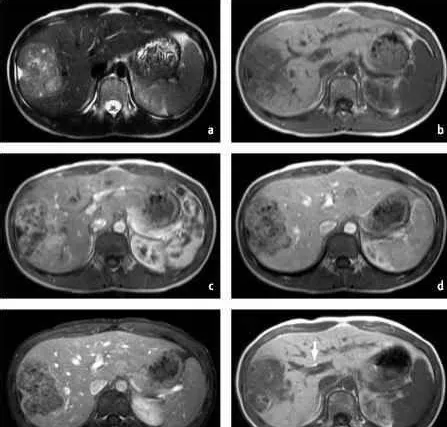

筛查手段最好的是影像学,目前阶段我国主要是依靠B超 AFP的方法,但绝对不可单独使用AFP。

image.png

有条件的情况下也可以使用MRI增强扫描,无电离辐射,能够发现足够小的肝癌,甚至对于癌前病变,比如肝硬化结节,退变结节等进行追踪和评估,而且可做到一站式检查,定位,定性,术前评估等。